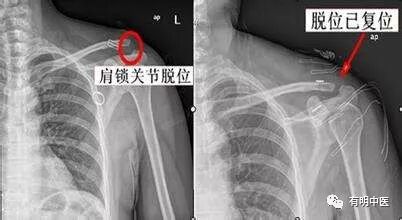

一、肩锁关节脱位

1、症状与诊断

患者多耸肩,肩关节酸痛。锁骨外侧方突起,局部肿胀,压痛明显,肩关节功能受限,上肢不能上举。在肩锁关节处可摸到横沟。指压锁骨外端时,可出现活动感。有些症状与肩周炎相似,有的患者被误认为肩周炎。